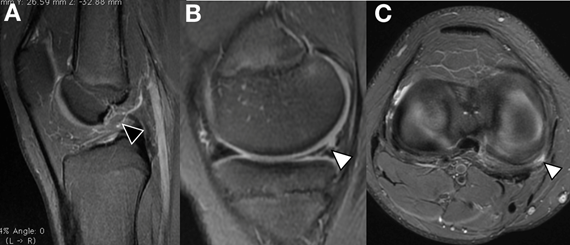

Consulta en el servicio de ortopedia infantil presentando al examen físico inestabilidad anterior dada por el test de Lachman positivo. Concomitantemente presentaba dolor a nivel de la interlínea interna, siendo positivas las pruebas de McMurray y Apley en relación al menisco interno. Se solicitaron radiografías anteroposterior (AP) y perfil (P) de la rodilla lesionada en busca de otras lesiones, siendo estas normales. Se solicitó una resonancia nuclear magnética (RNM) de la rodilla derecha, evidenciándose la rotura de LCA y una lesión longitudinal del cuerno posterior del menisco interno (Figura 1). Se coordina para cirugía artroscópica con el planteo de realizar una reconstrucción transfisaria del LCA y una reparación inside - out del menisco interno, al año de producida la lesión. Se realizaron en este momento los scores de Tegner & Lysholm, además del IKDC previos a la cirugía (Tabla 1 y 2).

Figura 1. RNM de rodilla derecha de paciente adolescente de 14años. A. Corte sagital en T2 que muestra (flecha negra con borde blanco) la ausencia de LCA. B y C. Corte sagital y axial en T2 que a su vez hace notar una lesión longitudinal periférica del cuerno posterior a nivel de la zona roja - roja del menisco interno (flecha blanca con borde negro).